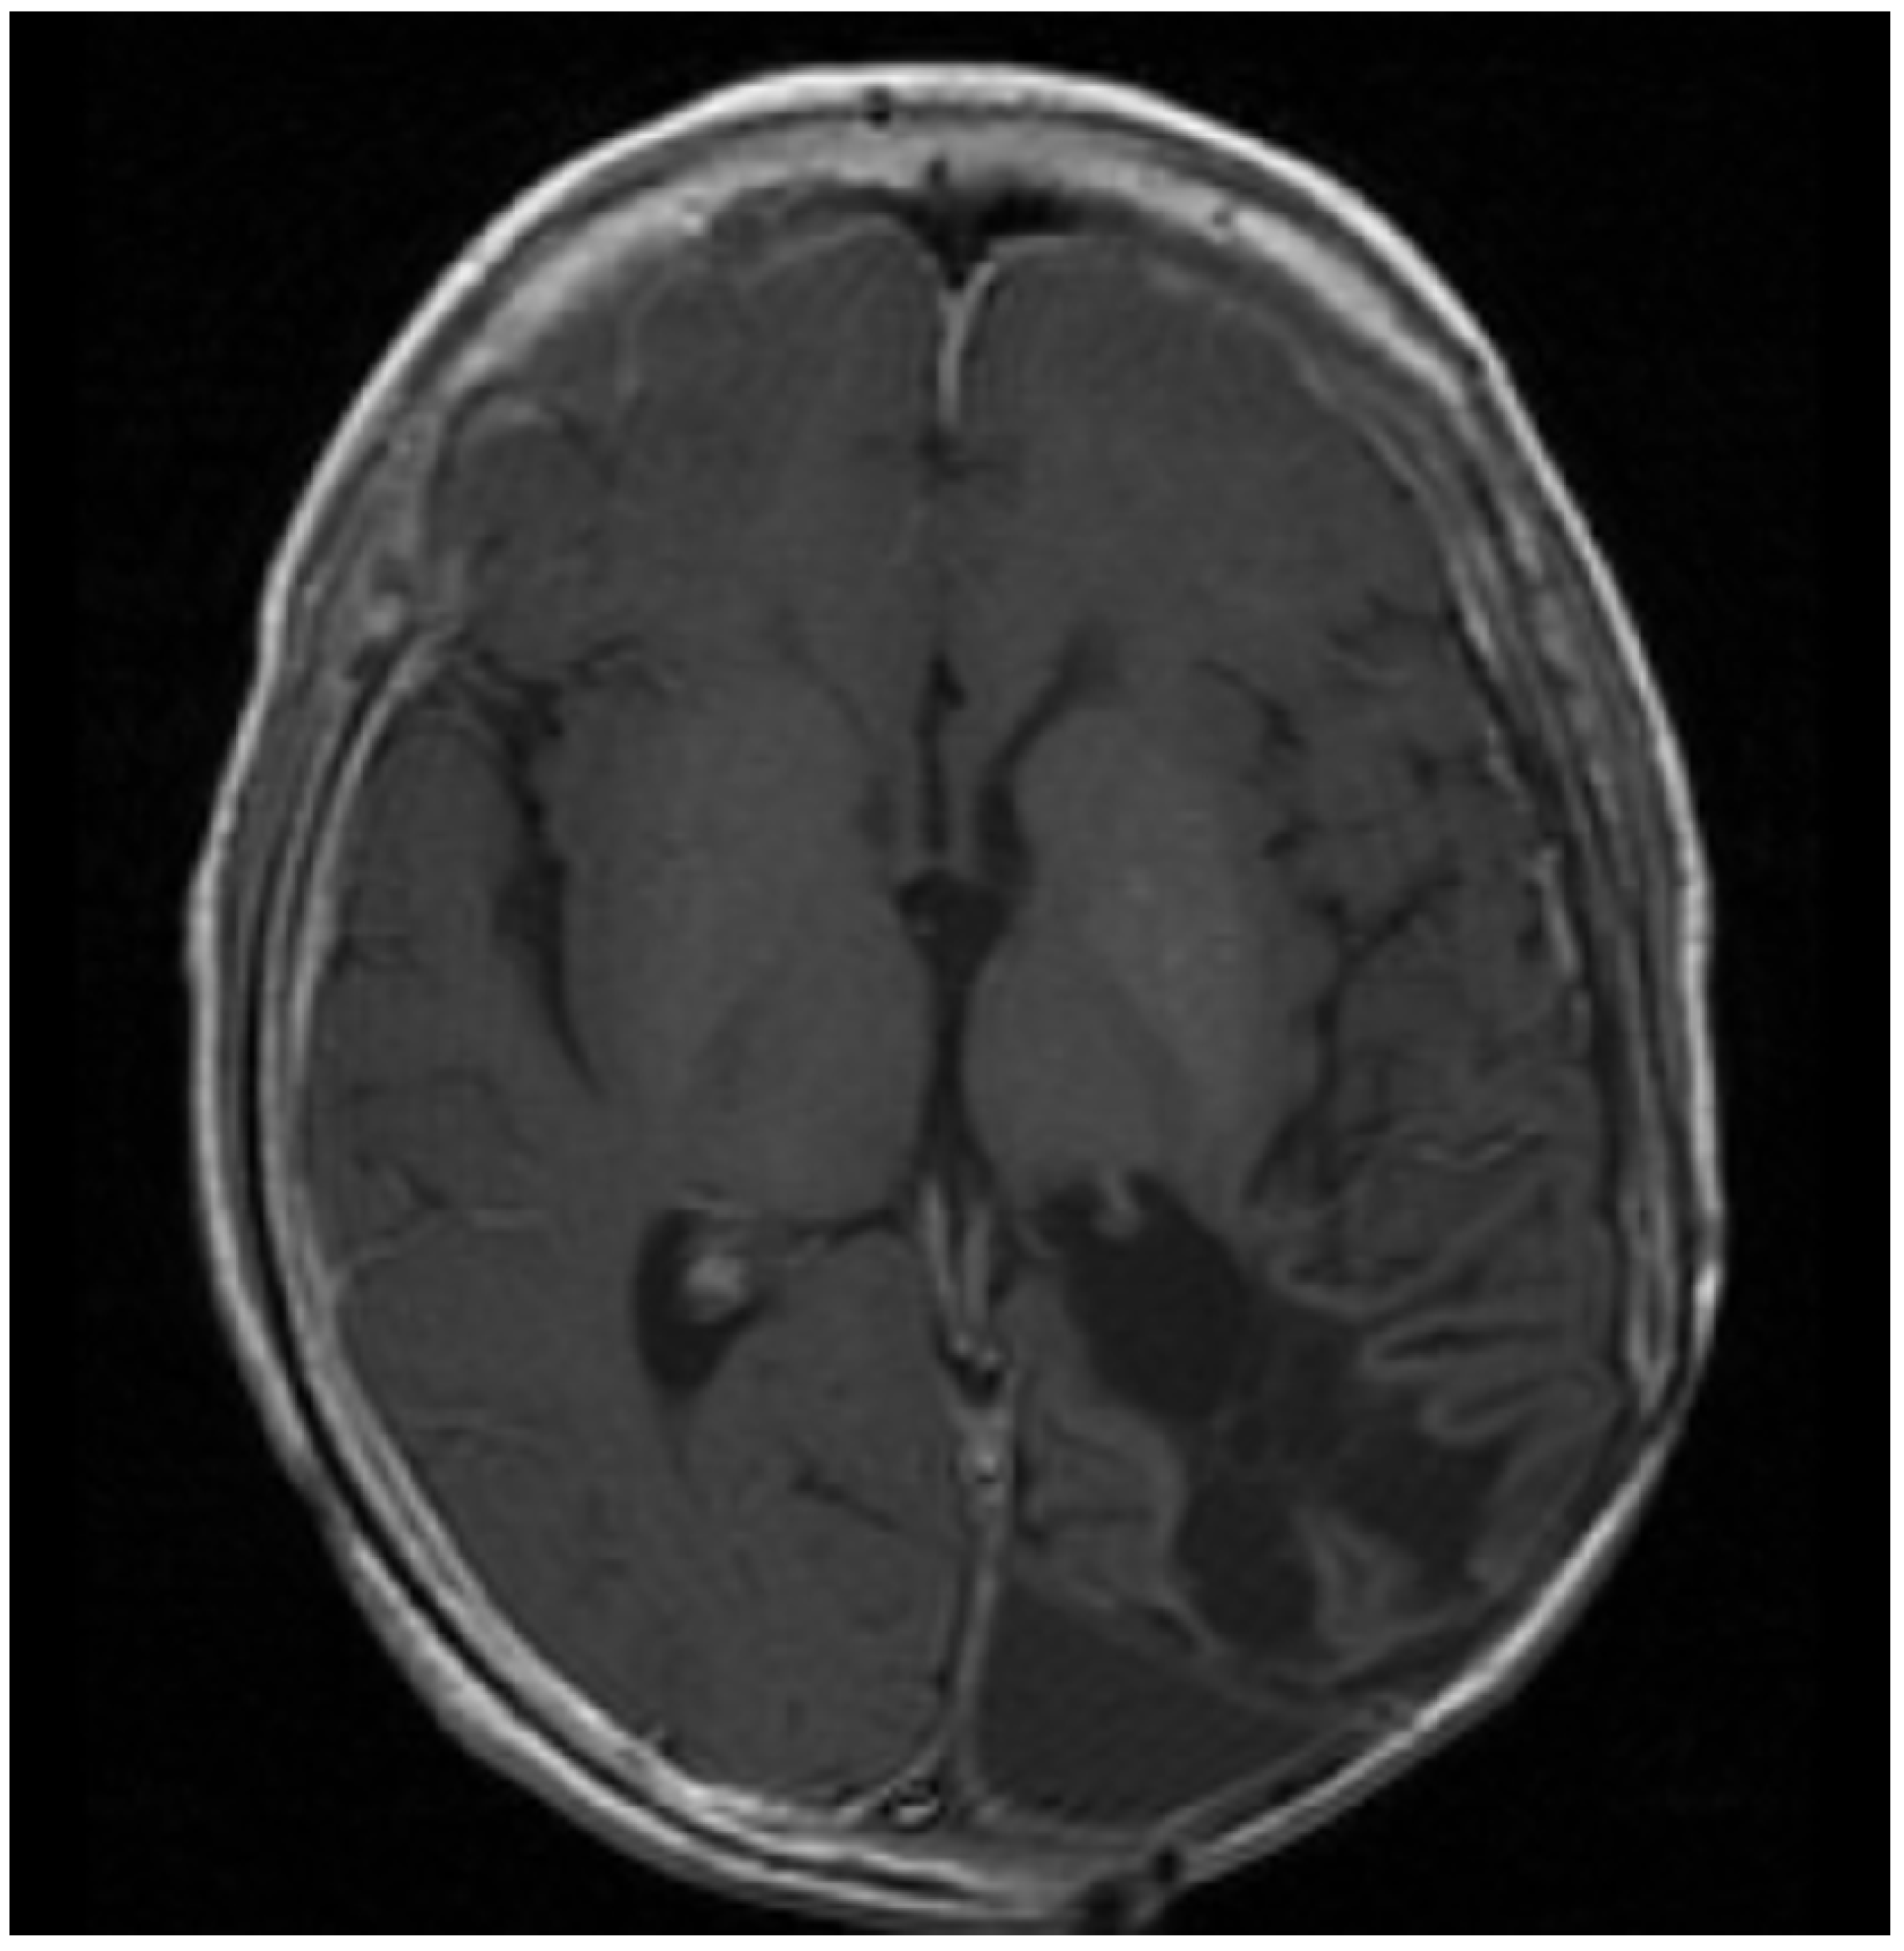

1.2. Patient 2

| 2 | Supratentorial Anaplastic Ependymoma. Local and distant relapse to spine. | VP16-CTX, Celecoxib, VA | 6 years | CR | CR 5.5 years at last encounter Alive 8 years at last encounter |